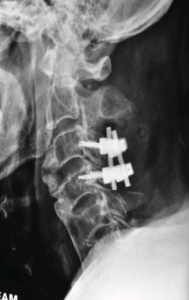

X-Ray of his cervical spine showed extensive ossification of posterior longitudinal ligament (OPLL) extending from C2 to C6 segments.

There was also presence of Diffuse Idiopathic Skeletal Hyperostosis (DISH). MRI of this cervical spine showed severe narrowing of spinal canal at C3-4 segment with cord compression and cord oedema. He was diagnosed as having severe central cord syndrome.

Because of the presence of proprioception in his right foot, the injury is deemed to be incomplete tetraplegia which implies the potential for recovery. The surgery consisted of C3 and C4 laminectomies to decompress the spinal cord. In view of the instability, C3 and C4 lateral mass plating were also performed to provide instrumented fusion on the 5th post injury day.